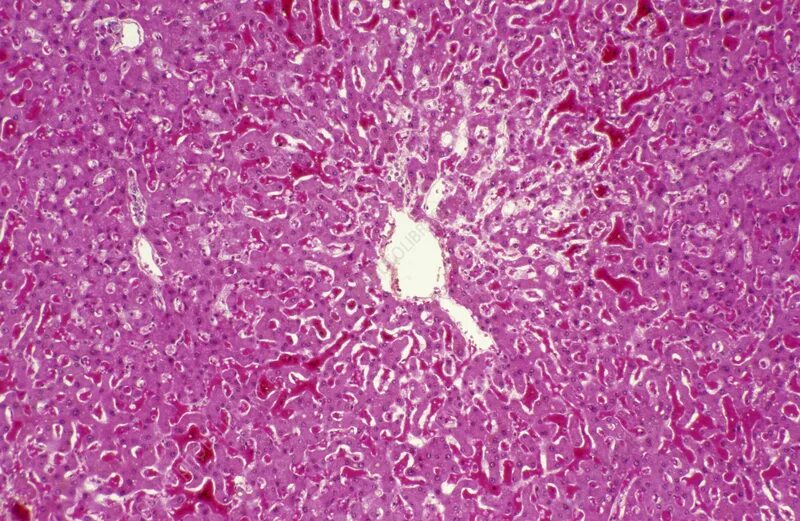

Структурная организация больших слюнных желез. Морфология секреторных отделов и системы выводных протоков. Печень: клеточные типы, характеристика классической печеночной дольки, портальной дольки и печеночного ацинуса. Кровоток и отток желчи. Морфология экзокринной части поджелудочной железы.